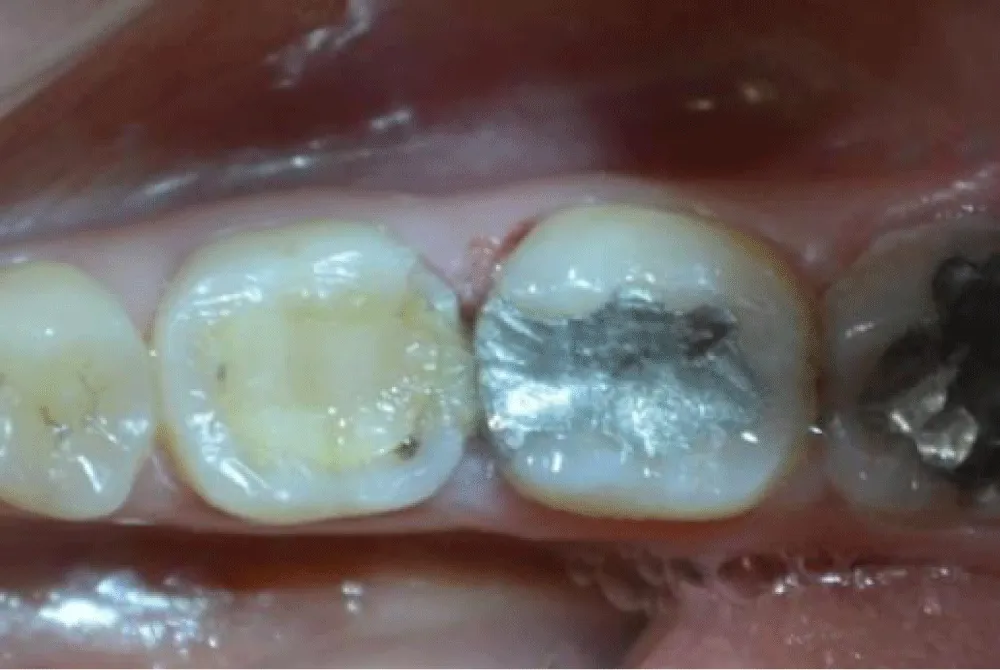

Clinical examination revealed two extensive posterior restorations affecting both tooth 36 and tooth 37, compromising the interproximal contours. Deep proximal-occlusal cavities associated with plaque accumulation in the interproximal space were detected. The probing of the interdental papilla showed localized bleeding confirming inflammatory changes in the adjacent periodontal tissues and compromised interdental architecture (Figure 1,2).

Radiographic evaluation confirmed the extent of structural loss. It demonstrated adequate endodontic treatment on the first molar, but insufficient coronal support (Figure 3). The second molar was vital. It also confirmed the lack of the natural interproximal contour, explaining the chronic irritation and pain which increases during mastication.